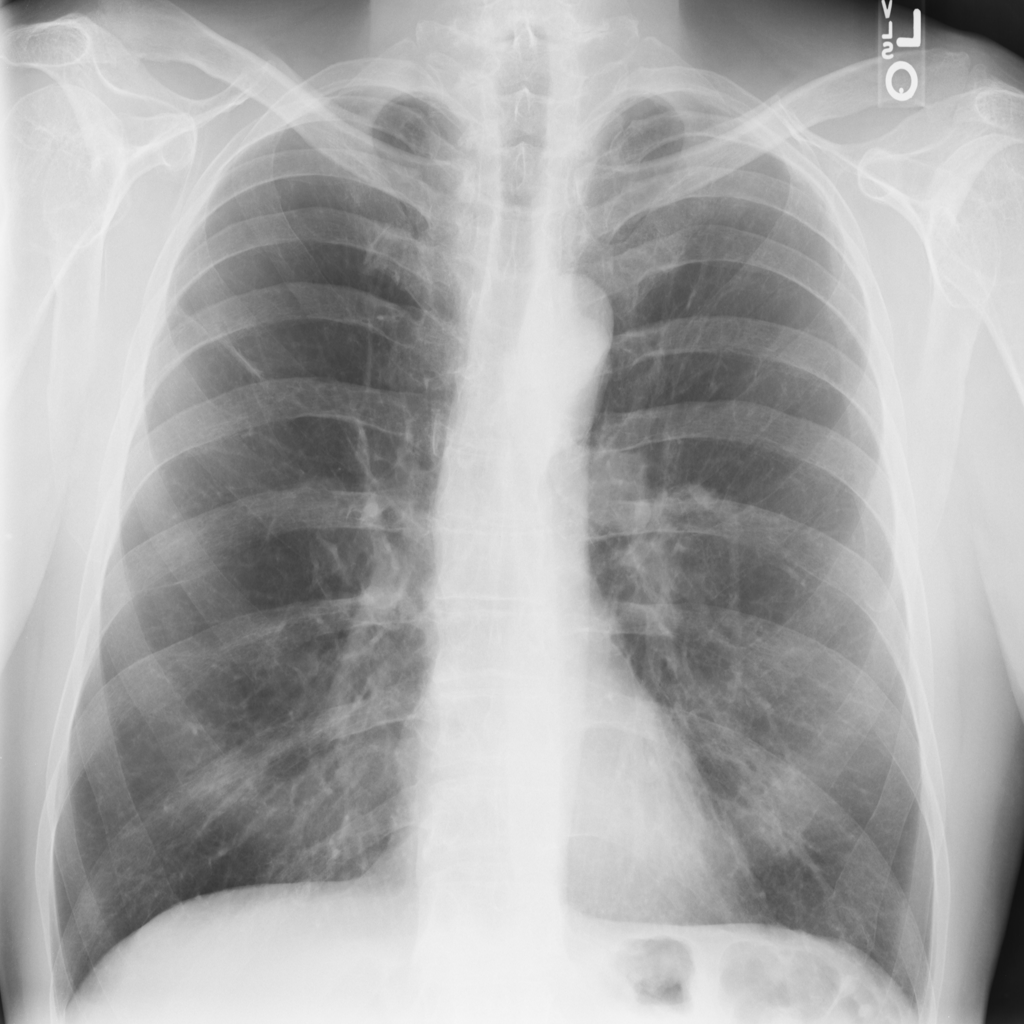

PAT-50E5 · IMG-008Mass

PAT-50E5 · IMG-008

PA